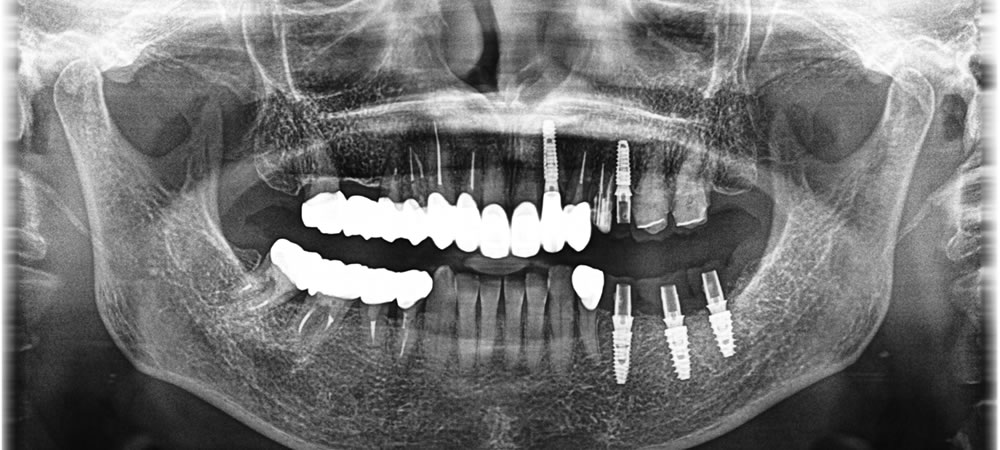

抜歯即時インプラントの実施

保存不可能な歯を抜歯した後、即時にインプラントを埋入しました。抜歯部分は骨量の減少も著しかったため、歯周組織の再生を促進するPRP(多血小板血漿)を同時に行いました。

上部構造の装着・治療完了

完成した上部構造を装着し、最終的な咬み合わせを調整して治療完了となりました。